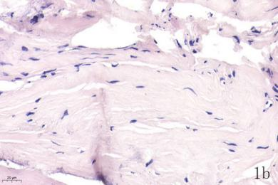

NDN(Necdin)属于黑色素瘤抗原(MAGE)家族,由60多个基因构成共享高度保守的MAGE同源结构域(MHD)[6,7]。最近几年的研究提出NDN是一种新的抑癌基因,其在卵巢癌[8]、乳腺癌[9]和黑色素瘤[10]等的组织和细胞系中低表达,过表达NDN可以抑制其生长,但NDN在骨肉瘤中的作用及机制尚不清楚。为探讨NDN在骨肉瘤中的作用及途径,我们收集了骨肉瘤患者的石蜡标本以及临床信息,对其进行了免疫组化检测及生存分析。通过对骨组织和骨肉瘤HE染色发现,骨组织组,骨密质呈板层状,陷窝中可见骨细胞呈梭形排列( 图1 a 1b) ;骨肉瘤组,瘤细胞呈多角形,核大深染,核分裂多见,瘤细胞呈车辐状排列,瘤细胞间可见少量肿瘤性骨质形成(图1c1d)。同时通过免疫组化发现,NDN表达主要位于细胞的胞核中。NDN在骨肉瘤组织中的表达率为29.4%(15/51)(图1c1d),明显低于瘤旁骨组织阳性表达率80%(8/10)(图1a1b)。